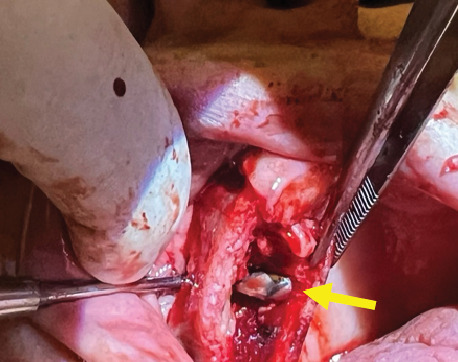

上颌窦潴留囊肿(msrc)是一种良性的充满液体的病变,通常在x线影像上偶然发现。虽然通常无症状,但较大的囊肿可能由于周围窦结构的压力而导致临床症状。本文报告一例罕见的MSRC症状病例,患者为70岁女性,有上颌磨牙拔牙后鼻窦穿孔病史。患者经历了严重的单侧面部疼痛、鼻塞、头痛和头晕,持续了6个月。x线影像(CT扫描)显示右侧上颌窦有一界限清楚的圆顶状病变,无骨侵蚀征象。鉴于保守治疗的失败和症状的强度,通过Caldwell-Luc入路进行手术干预。术中,囊性病变被去核并送去组织病理检查。组织学证实为呼吸上皮内衬的良性保留囊肿,伴炎症浸润和不寻常的胆固醇结晶,这在msrc中并不常见。患者的鼻窦穿孔史可能导致慢性炎症和囊肿形成。本病例强调了在出现非典型鼻窦症状的患者中考虑牙齿病史的重要性,特别是以前的上颌磨牙拔牙累及鼻窦。虽然内窥镜鼻窦手术通常是首选的方法,但Caldwell-Luc手术在某些解剖结构复杂或既往手术改变的病例中仍然有价值。临床医生应该意识到msrc的罕见表现可能需要量身定制的手术治疗来缓解症状和预防复发。

Maxillary sinus retention cysts (MSRCs) are benign, fluid-filled lesions most often discovered incidentally on radiographic imaging. Although typically asymptomatic, larger cysts may lead to clinical symptoms due to pressure on surrounding sinus structures. This report presents a rare symptomatic case of an MSRC in a 70-year-old female patient with a prior history of sinus perforation following upper molar extraction. The patient experienced severe unilateral facial pain, nasal congestion, debilitating headaches, and dizziness over a 6-month period. Radiographic imaging (CT scan) revealed a well-circumscribed, dome-shaped lesion in the right maxillary sinus without signs of bone erosion. Given the failure of conservative management and the intensity of symptoms, surgical intervention via the Caldwell-Luc approach was performed. Intraoperatively, the cystic lesion was enucleated and sent for histopathological examination. Histology confirmed a benign retention cyst lined with respiratory epithelium, along with inflammatory infiltrates and the unusual presence of cholesterol crystals, which is an uncommon finding in MSRCs. The patient's history of sinus perforation likely contributed to chronic inflammation and cyst formation. This case emphasizes the importance of considering dental history, particularly previous maxillary molar extractions with sinus involvement, in patients presenting with atypical sinus symptoms. While endoscopic sinus surgery is often the preferred approach, the Caldwell-Luc procedure remains valuable in selected cases with complex anatomy or previous surgical alterations. Clinicians should be aware of rare presentations of MSRCs that may require tailored surgical management for symptom resolution and recurrence prevention.